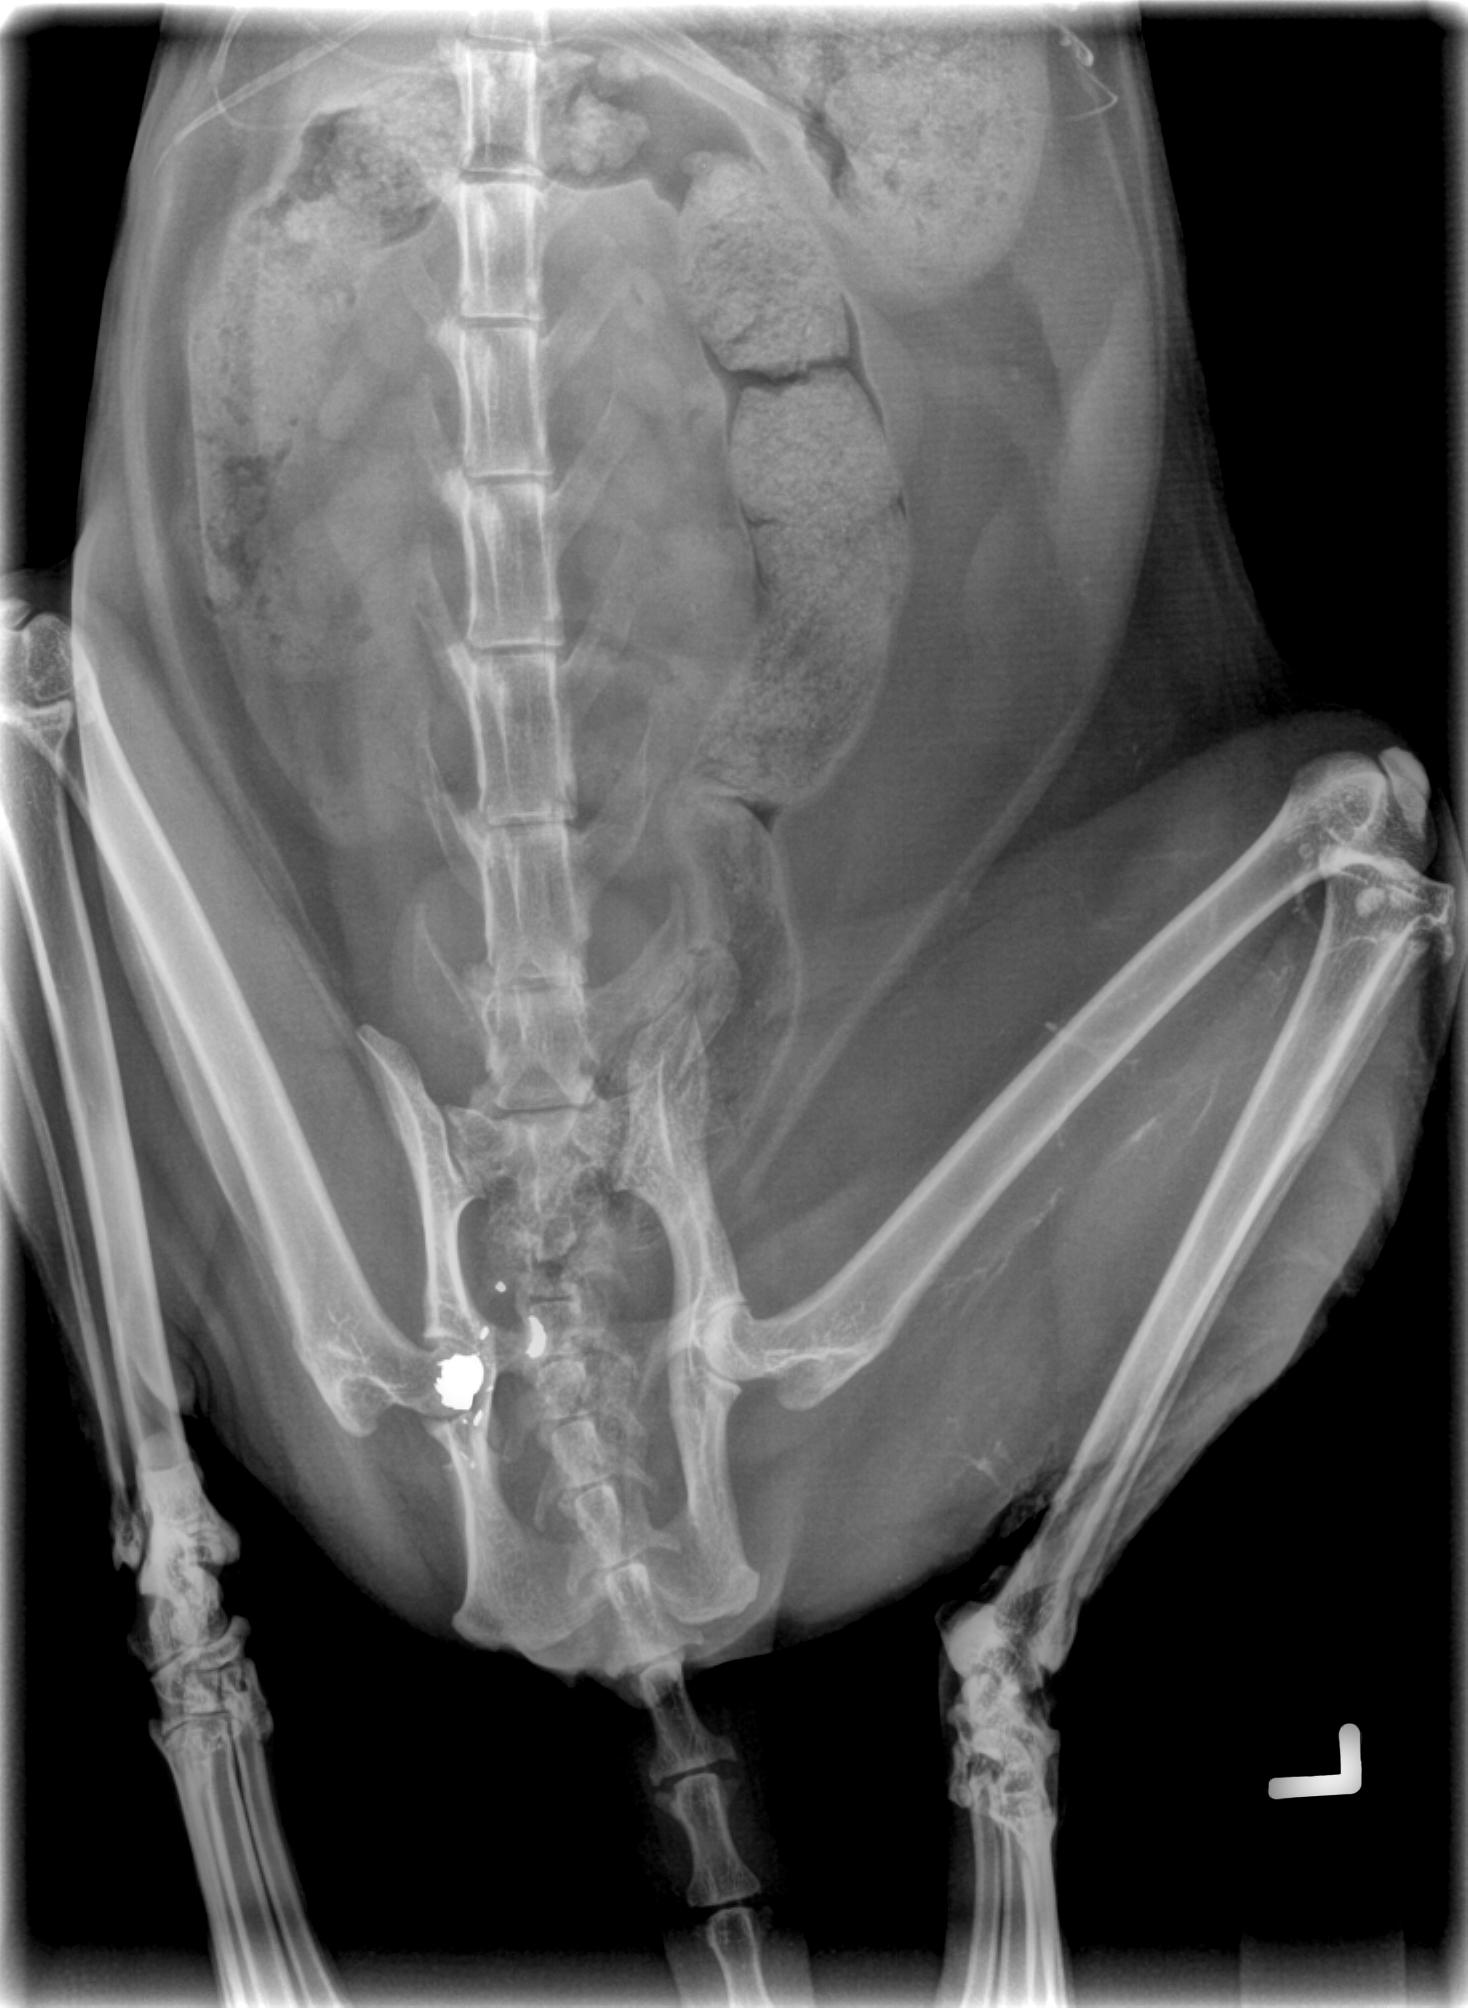

Pelvis cracked by impact of round, and you can see where some of it is way too close to the spinal column to go digging around.